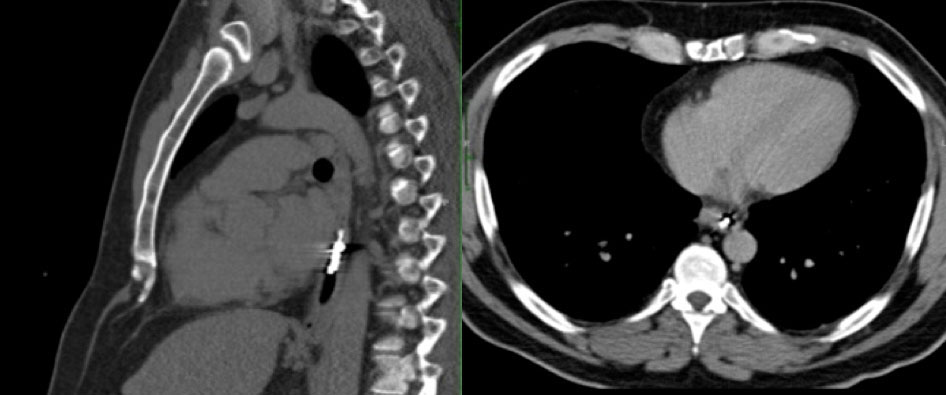

Case 12  67 year old man w/ampullary adenocarcinoma, status post whipple complicated by gastroduodenal artery hemorrhage necessitating hepatic artery stent. CT performed for follow up showed interval increase in biliary obstruction, narrowing of the portal vein confluence, concerning for recurrent tumor Axial CT and sagittal MPR demonstrate:

Case 12  67 year old man w/ampullary adenocarcinoma, status post whipple complicated by gastroduodenal artery hemorrhage necessitating hepatic artery stent. CT performed for follow up showed interval increase in biliary obstruction, narrowing of the portal vein confluence, concerning for recurrent tumor Axial CT and sagittal MPR demonstrate:

Migrated Hepatic Artery Stent

Migrated Hepatic Artery Stent